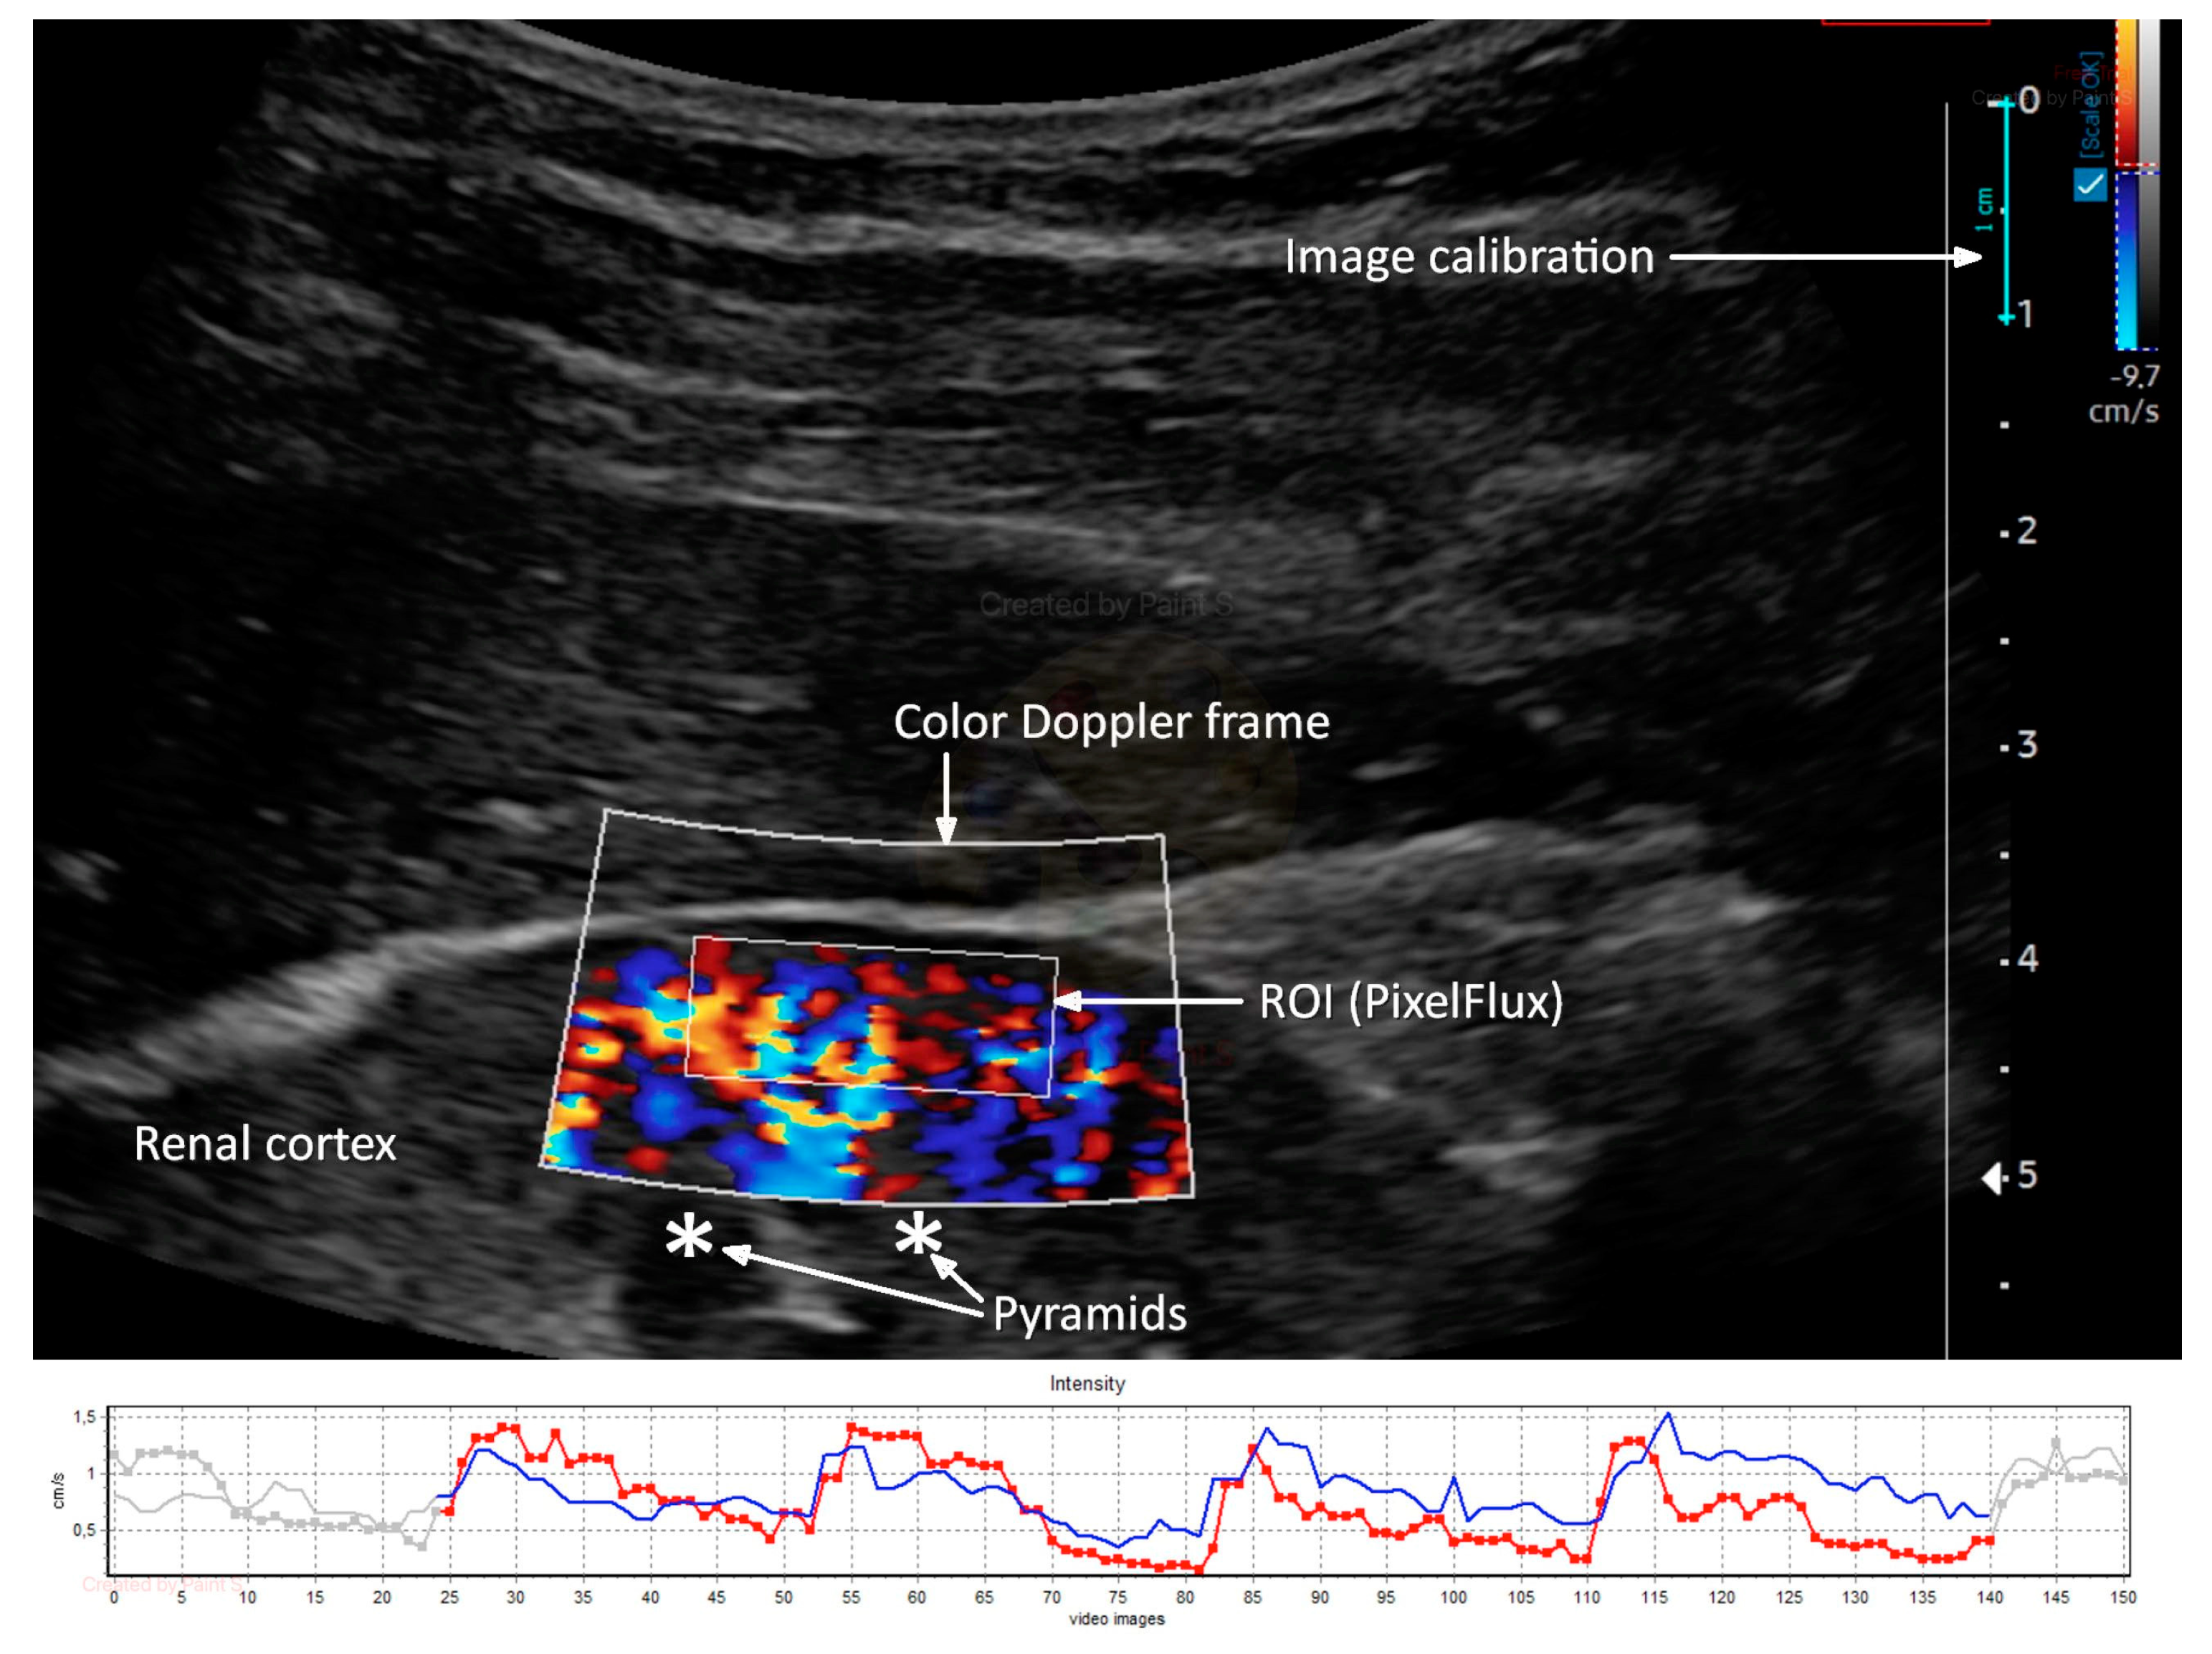

Renal Doppler ultrasound was conducted using an ultrasound machine (Samsung HS40, Suwon, Republic of Korea) equipped with a CA2-8AD (2–8 MHz) convex transducer. A color Doppler frame was positioned on the longitudinal portion of the right kidney cortex’s mid-segment to visualize cortical vessels directly heading the transducer. The color Doppler gain was set constantly and never changed. However, the flow velocity scale was set at 9.7 cm/s, which could be carefully adjusted to improve flow visualization and artifact prevention. To stabilize the image, the patient was instructed to stop breathing in the middle of the exhalation. Two to three DICOM-formatted movie files with the color Doppler picture sequences lasting three to five complete heart cycles were recorded. An external medical device was used to calculate Renal Cortical Perfusion (RCP) as the average arterial and venous flow intensity throughout the entire cortex in the studied section (PixelFlux, Chameleon Software, Leipzig, Germany). The region of interest (ROI) was placed on the renal cortex, free of focal abnormalities, between the kidney surface and the outer border of the medullary pyramids, and inside the color Doppler frame (Figure 2).

Figure 2.

Ultrasound color Doppler image of renal cortex perfusion, analyzed with PixelFlux software (upper part) with a graphical presentation of arterial (red) and venous (blue) flow intensity measurement (lower part). Own materials.